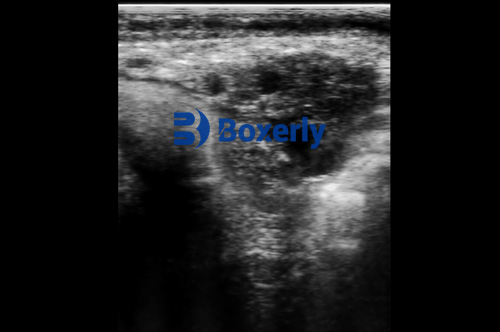

Veterinary ultrasound has revolutionized the way farmers and veterinarians assess the health of livestock. Unlike traditional diagnostic methods, which may require invasive procedures or lengthy lab tests, ultrasound provides real-time imaging of internal organs, tissues, and even fetal development. This technology is particularly valuable for detecting conditions such as pregnancy, tumors, cysts, and internal injuries without causing stress or discomfort to the animals.

- Organ Evaluation: Diagnosing liver, kidney, or heart conditions that may affect animal performance.